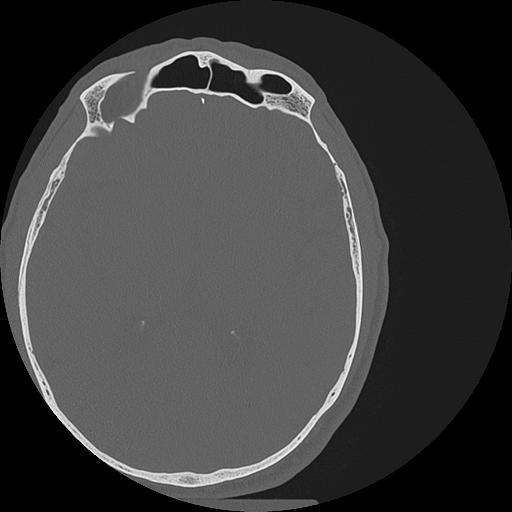

7 HUESO,,Vol,0.5,HUESO,,